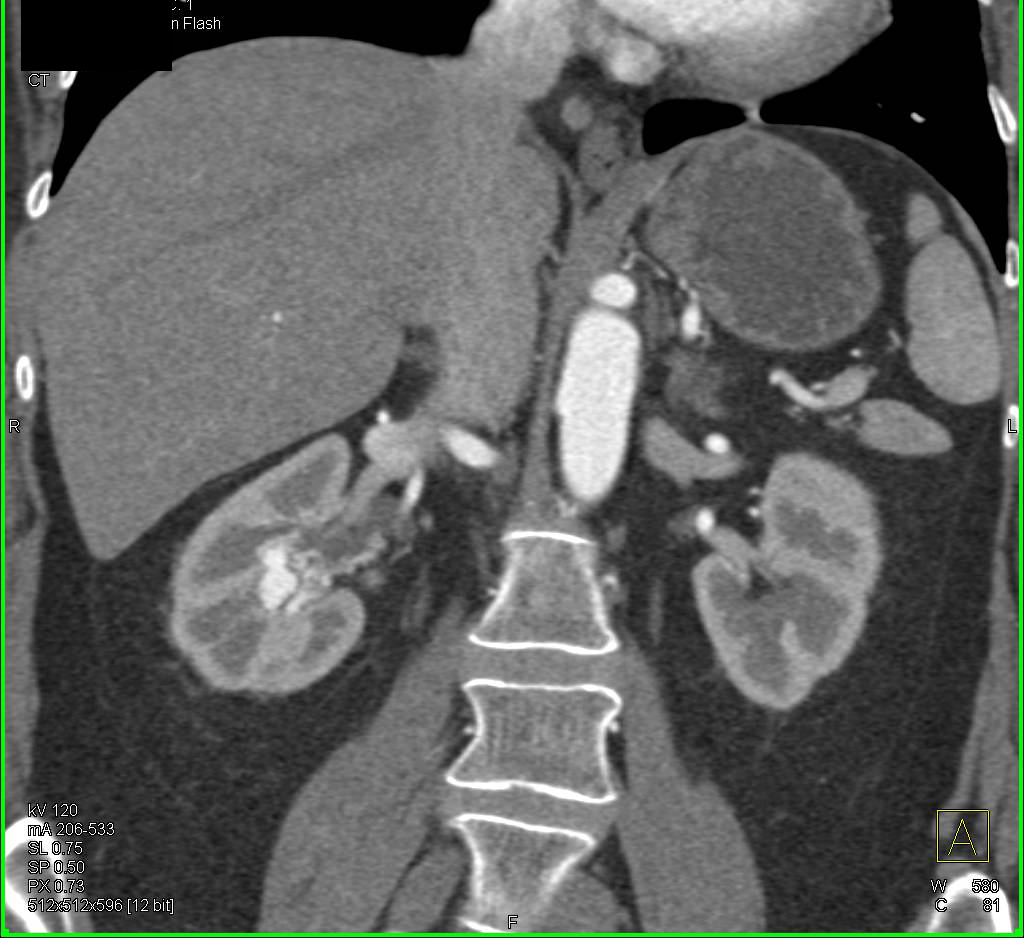

End Stage Renal Disease with Collaterals due to Superior Vena Cava (SVC) Occlusion